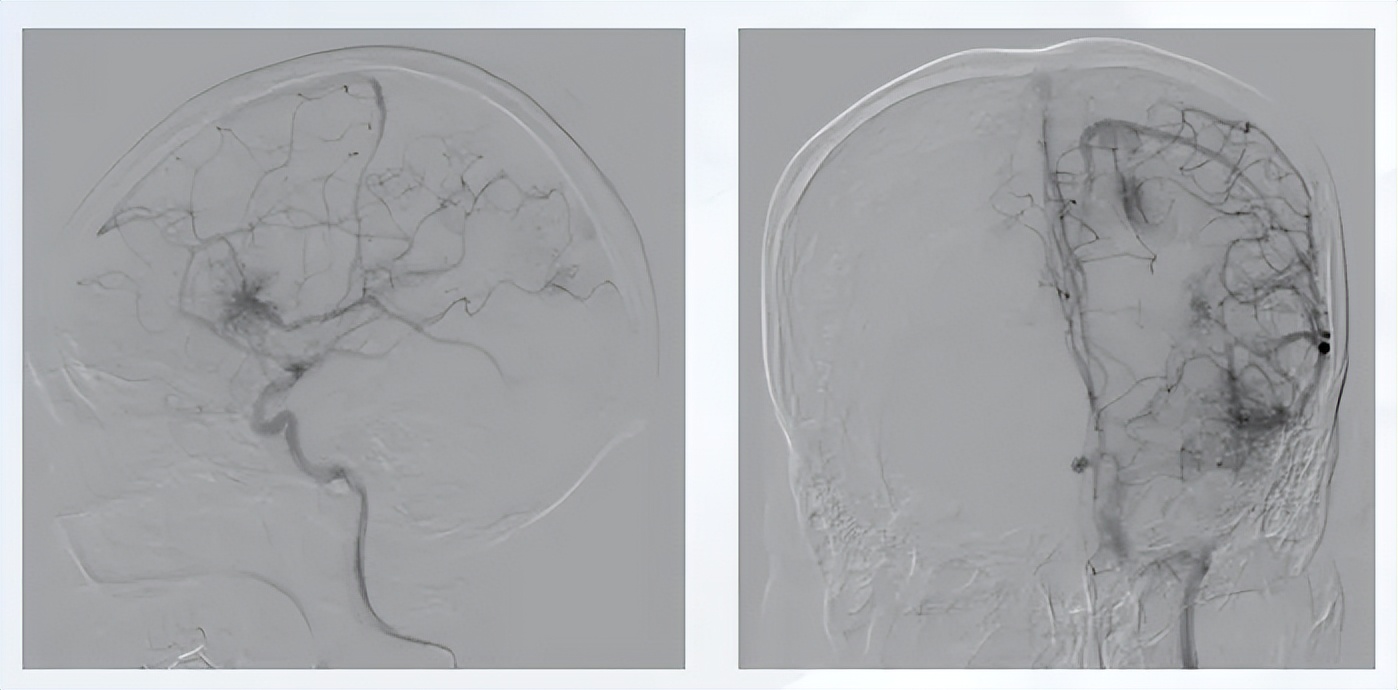

患者为少量出血,出血部位表浅,血管造影提示出血部位为小型动静脉畸形,供血动脉分支明确,引流静脉经海绵窦、翼状窦、乙状窦至上矢状窦。

图6 患者血管造影图

患者因行走偏斜2个月就诊,MRI检查提示颅内畸形,血管造影明确颅内存在5处动静脉畸形,累及双侧脑组织,同时合并硬脑膜动静脉瘘,右侧畸形可见静脉湖、深静脉引流及脉络膜前动脉动脉瘤。初始未发生破裂,因病变复杂未予手术处理,建议定期影像学复查。出院1个多月后患者突发意识障碍,头颅检查提示右侧颞顶叶大量出血。回顾术前影像,右侧畸形结构更为复杂,存在动脉瘤、深静脉引流等多个高危因素,与破裂危险因素的预测相吻合。

图7 右侧颈内血管造影

图8 左侧颈内血管造影

图9 左:左侧颈外血管造影;右:椎动脉血管造影